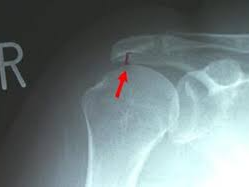

🔸 석회화 건염

힘줄 부위에 석회가 쌓이면서 심한 통증을 유발합니다. 급성으로 통증이 오고, 밤에 더 심해지는 경우가 많습니다.